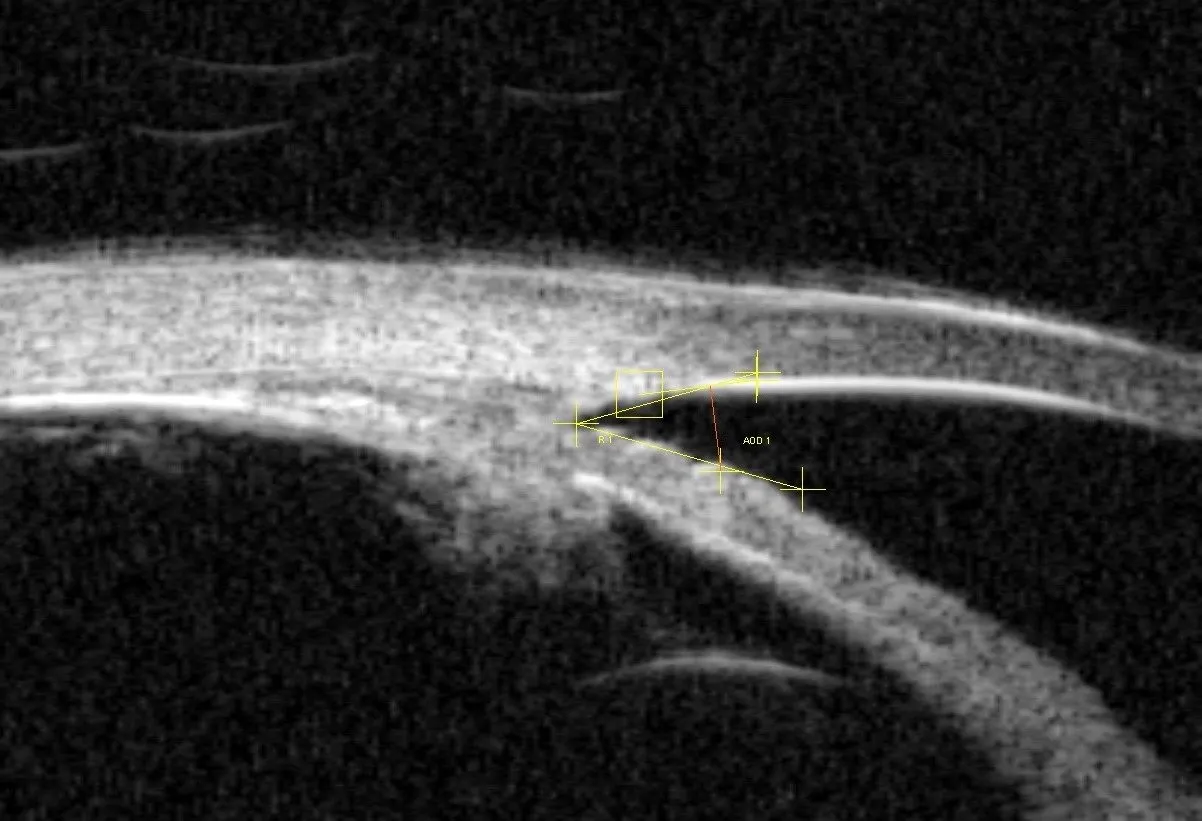

- Optyczna koherentna tomografia (OCT).

- OCT (optyczna koherentna tomografia): To nowoczesne, nieinwazyjne badanie obrazowe, które pozwala na precyzyjną ocenę grubości włókien nerwowych siatkówki oraz struktury tarczy nerwu wzrokowego. Dzięki niemu mogę wykryć nawet bardzo wczesne zmiany, zanim pojawią się ubytki w polu widzenia.